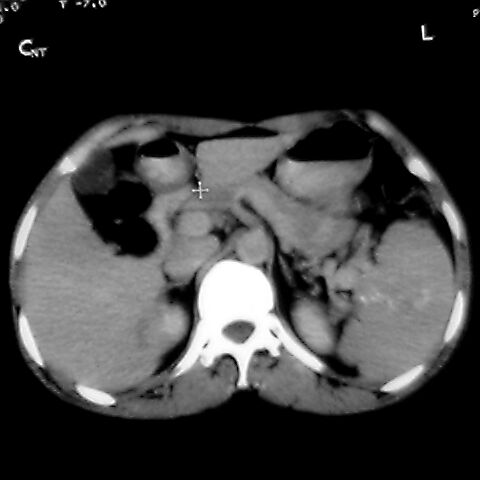

女 48岁 食道癌术前体检发现脾占位。

脾胀内部巨大低密度肿块,边界清或不清,中心坏死,轻度增强,内见散在钙化,结合食道癌病史多考虑:转移癌.

考虑脾脏血管瘤,中央低密度为血栓形成

脾脏低密度灶伴钙化,增强化明显,中心见液化坏死灶,强化延时明显。考虑血管瘤。转移瘤待排。